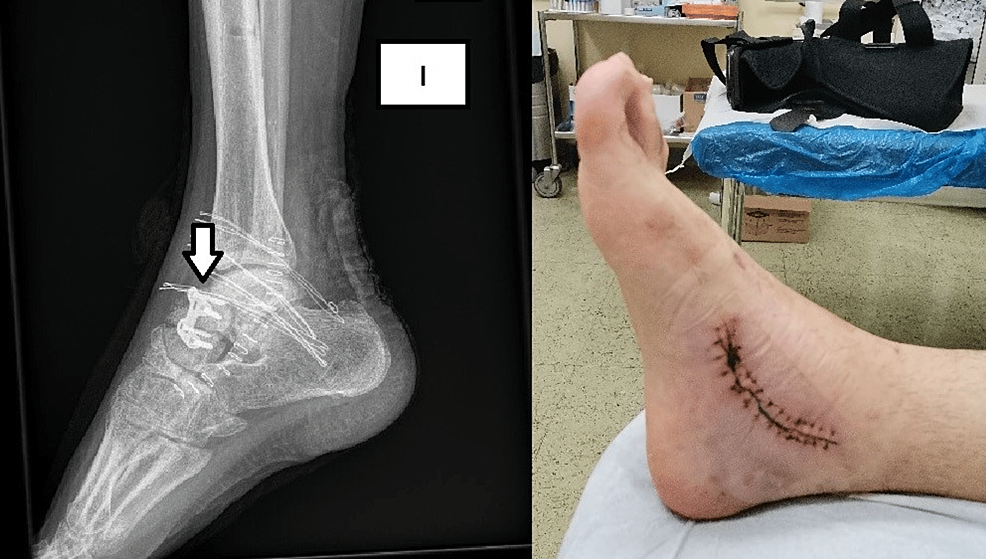

From www.cureus.com

Posttraumatic Cavovarus Deformity Due to a Varus Malunited Talar Neck Talus Bone Deformity Congenital vertical talus is a rare congenital condition caused by neuromuscular or chromosomal abnormalities in neonates that typically presents with a rigid. Vertical talus is a rare deformity of the foot that is diagnosed at birth. Congenital vertical talus is a foot deformity characterized by dorsal dislocation of the navicular resulting in equinus and hindfoot. It is one of the. Talus Bone Deformity.